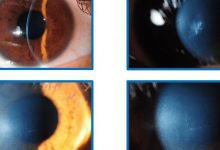

圆锥角膜 教科书式解释: 根据目前的最新国际研究现状,圆锥角膜(keratoconus)是一种常见的非炎症性、慢性、进展性、角膜局部扩张性疾病,以角膜扩张、中央或旁中央变薄向前突出,呈圆锥...